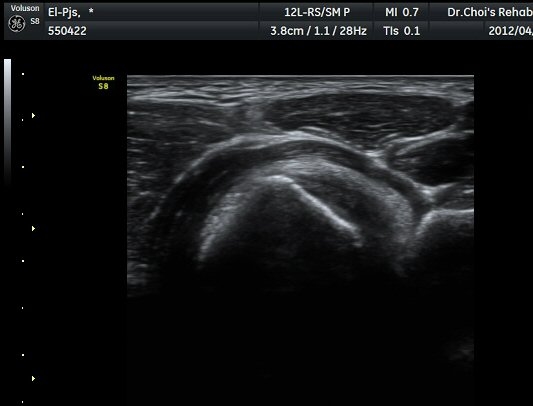

¾Æ·§ÆÈÀ» ¿ÏÀüÈ÷ ȸ³»ÇÑ »óÅ¿¡¼­ ÆÈ²ÞÄ¡°üÀý 1.5cm ¾Æ·¡¿¡ ŽÃËÀÚ¸¦ ȾÀ¸·Î ´ë´Ï ¿ä°ñ°ú

ºñ°ñÀÌ °üÂûµÇ°í ±× »çÀÌ¿¡¼­ À̵ιڱ٠ÈûÁÙ ºÎÂøºÎ°¡ °üÂûµÈ´Ù(±×¸² 7). ŽÂÊÀÚ¸¦ Á¾´Ü¸éÀ¸·Î

À§Ä¡ÇÏ´Ï ¿ä°ñµ¹±â¿¡ ºÎÂøµÈ À̵ιڱ٠ÈûÁÙÀÌ ¶Ñ·ÈÈ÷ °üÂûµÈ´Ù(±×¸² 8).